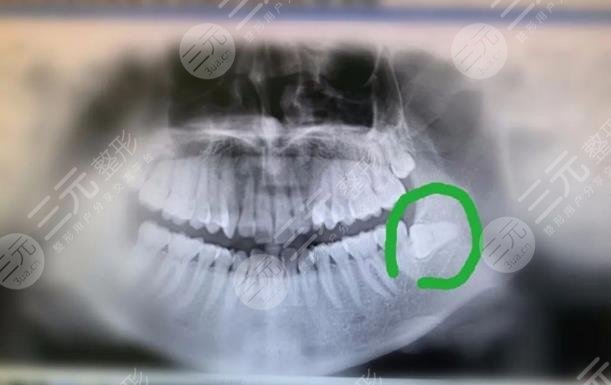

During that period of time, I was really tormented by wisdom teeth and couldn't sleep, I felt no energy every day, and my friends around me also looked at my face, which became more and more swollen, and they all said that if it dragged on like this, it might have a greater impact on my health, and I myself was more resistant to going to the hospital, so it took a long time. Later, I couldn't stand the pain anymore, so I went to Foshan Yadu Dental Hospital at the recommendation of a friend.

After going to the hospital for an examination, it was determined that the wisdom teeth could be removed, and the operation was performed soon after, and the anesthetic was injected during the operation, so it did not feel much pain, but the process was still a little uncomfortable. But when the strength of the anesthetic passed, the pain became more and more obvious, and the face became more and more swollen, and it was more difficult to eat, but the thought that it would not hurt after a week still had some comfort in my heart.